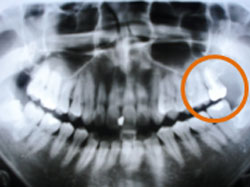

ところが根管は歯の種類によって形も複雑で手探りの作業になるため、時間をかけて丹念に行わないと先端まで十分に行き届かず、後になって根の先に病気が出てしまう原因となります。当院では最新の薬剤3MIX-MP法の併用で難しい根管治療を徹底して行っております。

※歯の形は複雑に異なり、根っこの本数もそれぞれです。